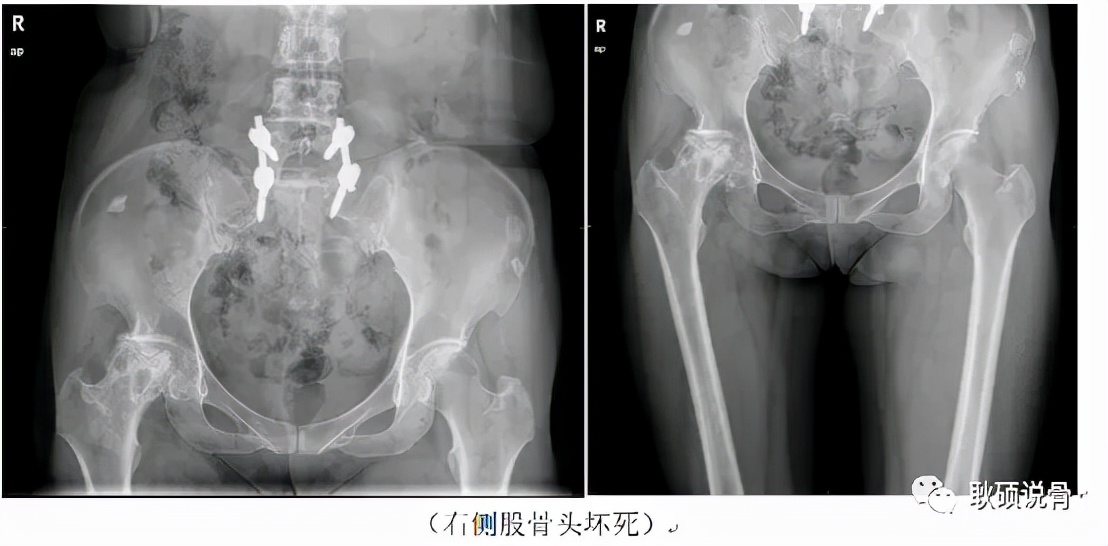

我在门诊见到她时,是丈夫推着轮来的。在对孙女士的基本情况进行充分的了解后,我对她进行了详细的查体。结果在我的意料之中:她的右侧Thomas征和“4字试验”均为阳性的,右侧髋关节的活动度明显受限,尤其是髋关节的内收外展功能。简单地说,就是“劈不开腿”。在完善骨盆正位X光片后,结果再一次印证了我的判断,她的右侧股骨头内部可以见到明显的囊性变(即密度减低,出现空洞),股骨头已经变形塌陷,髋关节间隙明显变窄,并且髋臼也受到了累及,出现了骨赘(即老百姓所说的骨质增生或“骨刺”)和硬化。根据病史、体格检查和影像学表现,可以明确诊断为“股骨头坏死”,并且已经是终末期。